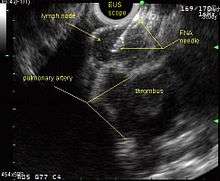

Endoscopic ultrasound (EUS) is an endoscopic technique where a miniaturized ultrasound probe is passed though the mouth into the upper gastrointestinal tract to investigate organs and structures close to the esophagus, stomach, or duodenum, such as the lung. In 1993, Wiersema published the first description of EUS to diagnose and stage lung cancer,[27] done by advancing a fine needle through the esophagus into adjacent lymph nodes. Numerous subsequent studies have shown this general methodology to be effective, very safe, minimally invasive, and very well tolerated. Given these advantages, many authorities think that EUS together with endobronchial ultrasound (EBUS) enhances lung cancer diagnosis and staging.[28]

Endoscopic ultrasound (EUS)

A metaanalysis published in 2007, based on 1,201 cancers in 18 high-quality clinical trials carefully selected by predefined criteria from the literature, systematically examined the performance of EUS-guided FNA in NSCLC staging. Two scenarios were considered: the setting of enlarged lymph nodes on CT (suggestive but not diagnostic of cancer), and the obverse scenario of an absence of lymph node enlargement on CT (suggestive but not diagnostic of no cancer).[24] Overall, in both settings, minor complications were reported in 0.8% of procedures; no major complications were recorded. EUS-FNA in enlarged discrete mediastinal lymph nodes had an excellent pooled sensitivity (8 studies) of 90% (95% CI, 84 to 94%) and specificity of 97% (95% CI, 95 to 98%). EUS-FNA in the setting of no enlarged mediastinal lymph nodes on CT had a pooled sensitivity (4 studies) of 58% (95% CI, 39 to 75%) and specificity of 98% (95% CI, 96 to 99%). Although this sensitivity (58% in CT-negative disease) might on first consideration seem disappointing, if EUS is performed as a staging test it can help avoid more invasive staging procedures, or surgery, if positive (for the presence of cancer). In other words, an EUS that has a positive result (shows cancer) will avoid further needless surgery, whereas a result not showing cancer may be false-negative, and probably requires an excisional biopsy technique for confirmation, such as VATS or mediastinoscopy.

EUS can reliably reach the lymph node stations 5, 7, 8 and 9. In the superior mediastinum the trachea is somewhat to the right of the esophagus which makes it often possible to reach left-sided area 2 and 4 lymph nodes and, less often, right sided paratracheal lymph nodes.[29] In general, EUS is most appropriate for evaluation of the posterior inferior mediastinum while mediastinoscopy or EBUS are best for the anterior superior mediastinum. The feasibility of EUS-FNA of aorto-pulmonary window (subaortic) lymph nodes (station 5) is a major advantage of EUS. Evaluation of this station has traditionally required a paramedian mediastinotomy (Chamberlain procedure). EUS can easily sample celiac lymph nodes, which cannot be reached by the other mediastinal staging methods. In one recent study an unexpectedly high incidence of celiac lymph node metastasis (11%) was noted.[30] EUS can also be used to biopsy potential left adrenal metastases, whereas the right adrenal gland is mostly inaccessible.[31]